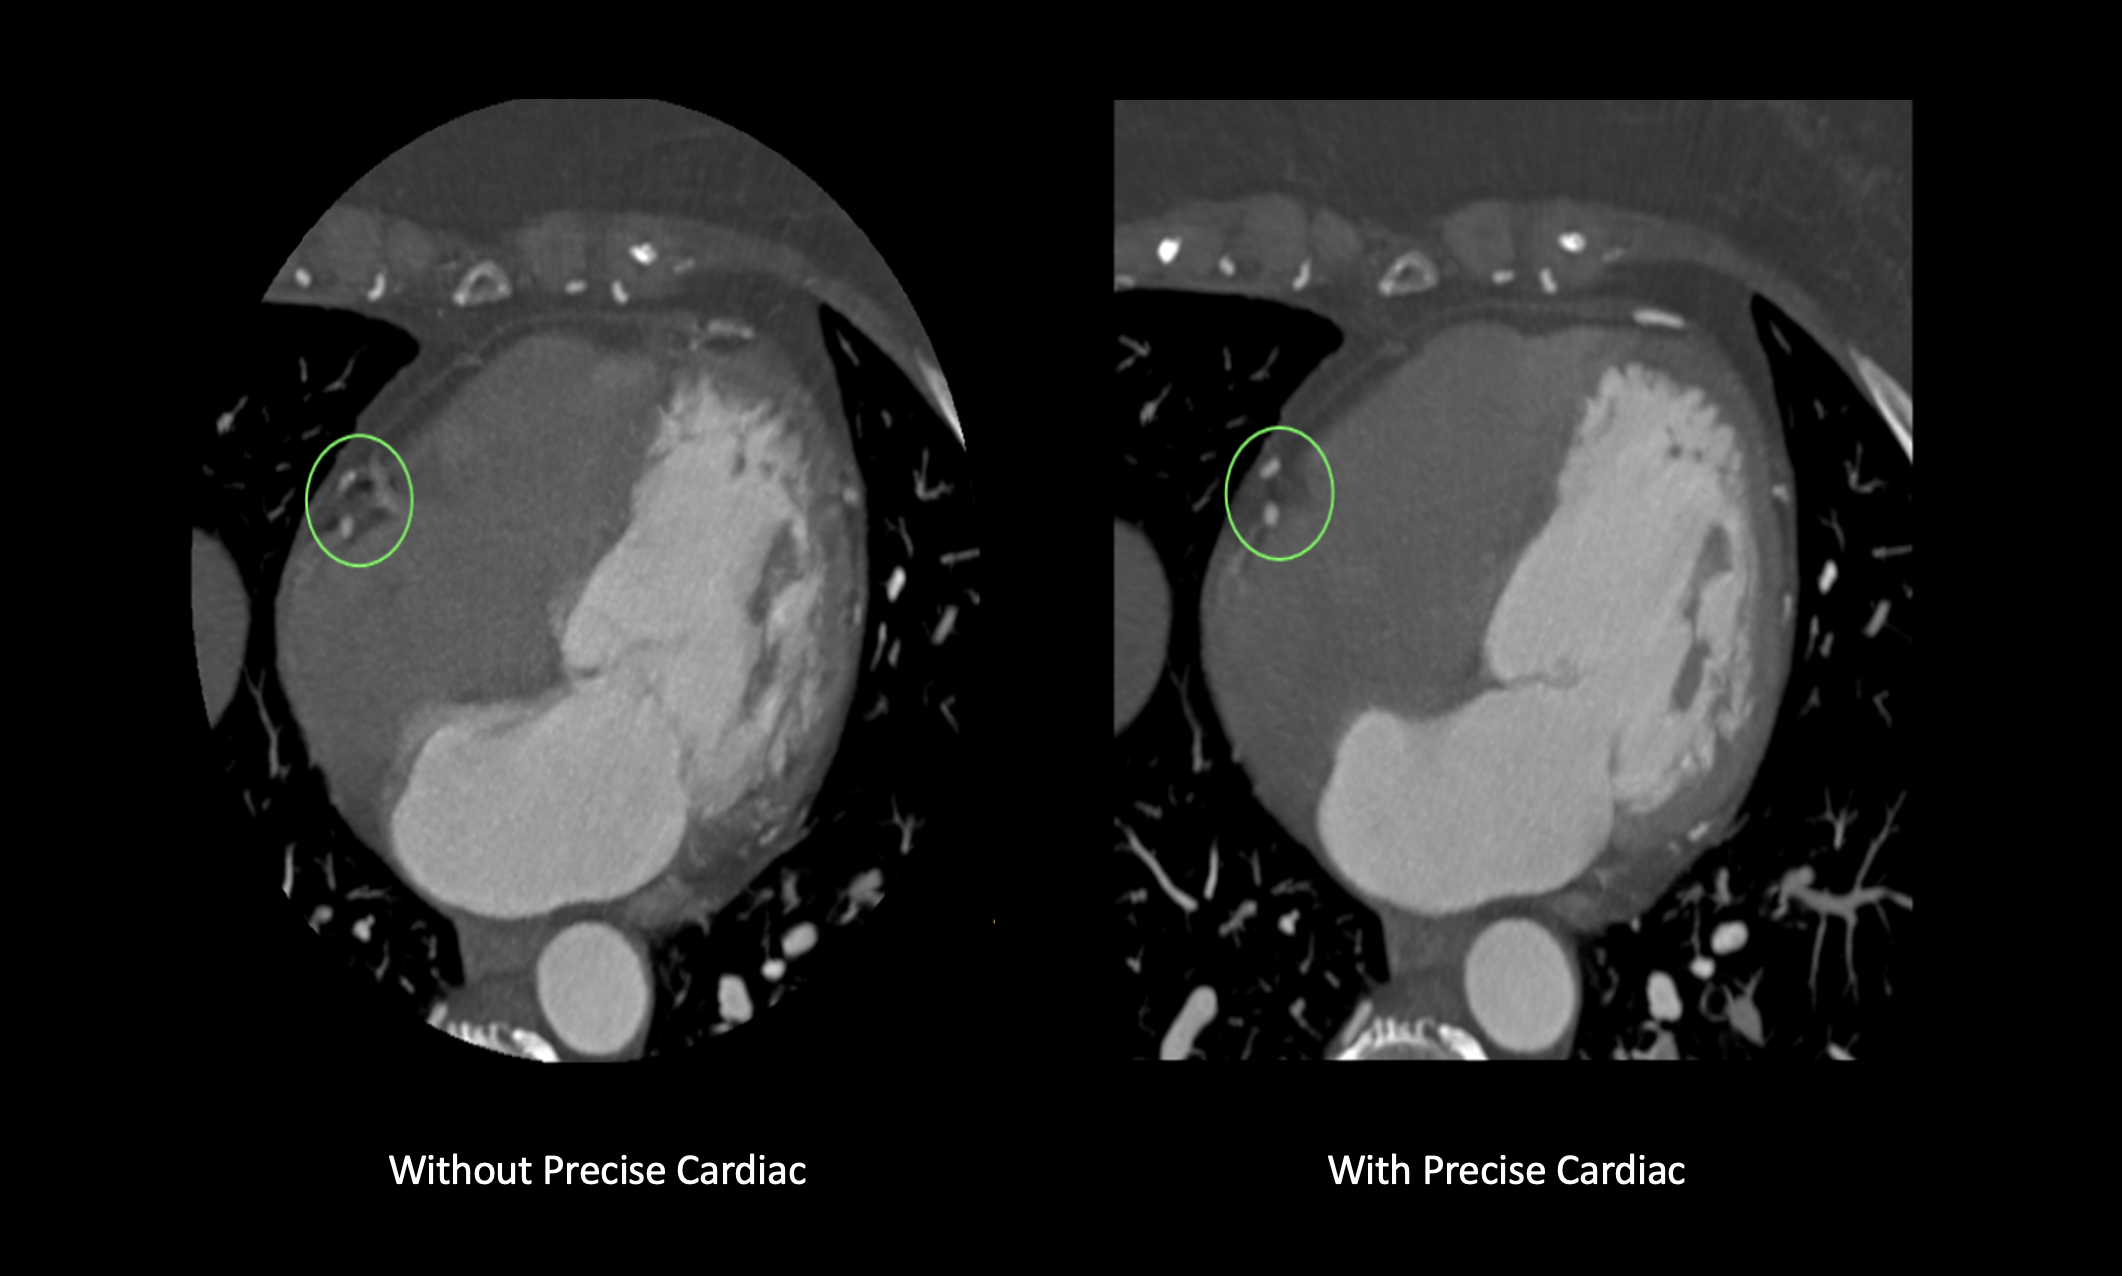

Precise Cardiac is a reconstruction technique that compensates for cardiac motion to improve visualization of the coronary arteries during CT imaging. This enables clinicians to see what’s happening in the coronary arteries.

Precise Cardiac demonstrates significant improvements in image quality of the coronary arteries, compared with standard cardiac CT reconstructions. Applicable for different types of CT exams (retrospectively gated helical exams and prospectively gated axial exams), Precise Cardiac employs efficient filtering techniques in a predefined region around the targeted cardiac phase to identify relevant objects and dynamically track their motion behaviour in the localized portion of the cardiac cycle. Motion-corrected images are generated by taking into account the displacement of structures and performing the relevant corrections as part of the reconstruction process.

Precise Cardiac is built into the CT workflow, avoiding the need for any manual intervention by the person doing the scanning, the need for data transfer or the need for additional workstations. It improves diagnostic confidence in challenging patients with high or irregular heart rates and can help a clinician salvage some coronary segments previously deemed nondiagnostic using standard cardiac reconstructions, thus increasing diagnostic confidence in coronary CTA exams. Coronary motion correction can potentially reduce the need for a repeat scan.